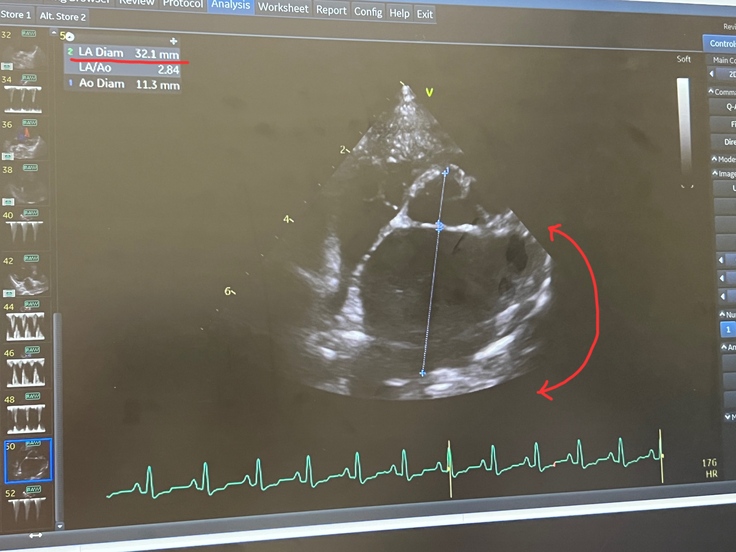

↑心臓もかなり肥大しています。